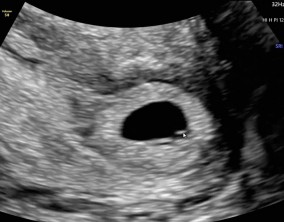

임신 수치 16, 9주차 기적의 기록

서울IVF에서는 단순히 배아 생성과 이식만 해주시는 것이 아니라, 제 생활 전반까지 신경 써주셨습니다. 휴식기에도 그저 기다리는 것이 아니라 항노화에 도움이 되는 링겔을 처방…